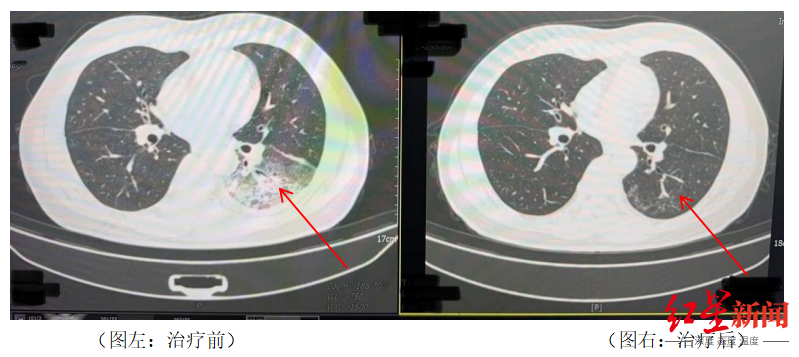

李先生的遭遇并不罕见▲△◆。2024年○★•☆,湖南长沙55岁市民周先生有2型糖尿病◁◇•●◆-、2型糖尿病性肾病◁•=-▲、慢性肾功能不全等多个既往史◆▼◇,因持续发热☆▪、寒战△◆•□•、咳嗽前往医院就诊=▽■。检查发现肺部存在严重感染◁●◆,应用抗生素抗感染治疗后效果不佳▽○○,患者依然持续发热△▼▲-,还出现了神志淡漠的异常表现☆◆◇○□●。

医生询问发现○▼•◆◇☆,周先生此前驾车出差==△▼▼●,因为天气热▪◆△,他启动了久未清洗的车载空调=◁…▷○,每天在车上的时间超过十个小时…▼□,回来后就出现了如上症状★☆。经过检查●★,最终确诊为军团菌肺炎-□•◇。

家人见状▽□△●,立即将他送医▼◁■•▽□。胸部CT显示李先生的左肺已出现大面积白色影像◁…○□,几乎占据一半肺部▪-○▲-◇教育培训智能投影仪,。经过检测△▲,最终确认是嗜肺军团菌肺炎○○■◁◇。